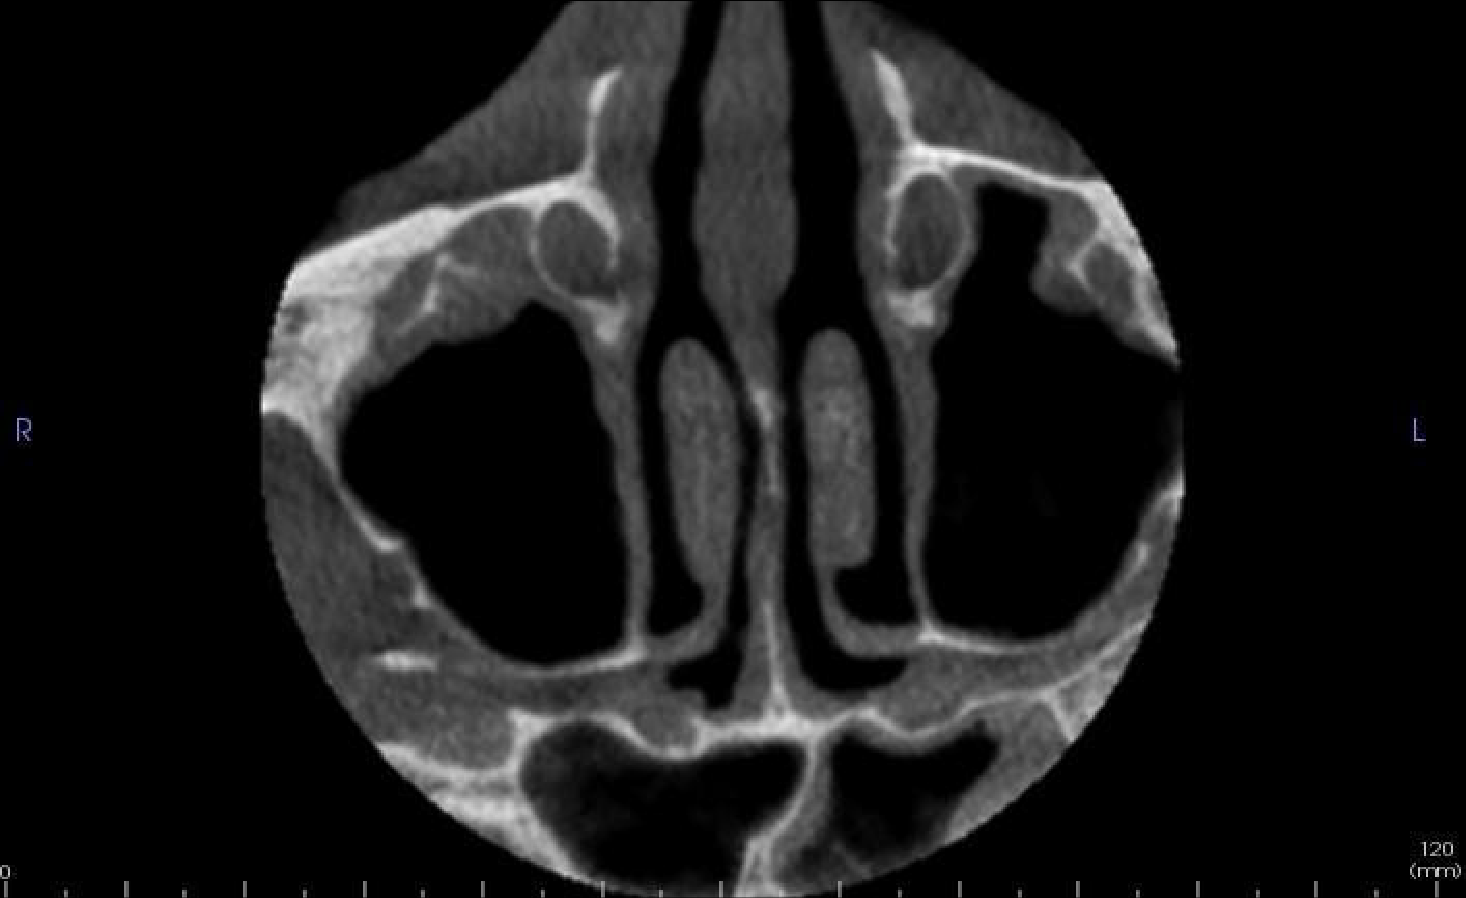

Axial and coronal slices showing mucosal lining thickening of the left sphenoid sinus

Both maxillary and left sphenoid sinuses have mild generalised thickening of the mucosal linings. There is no expansion or bony erosion of the sinus walls.